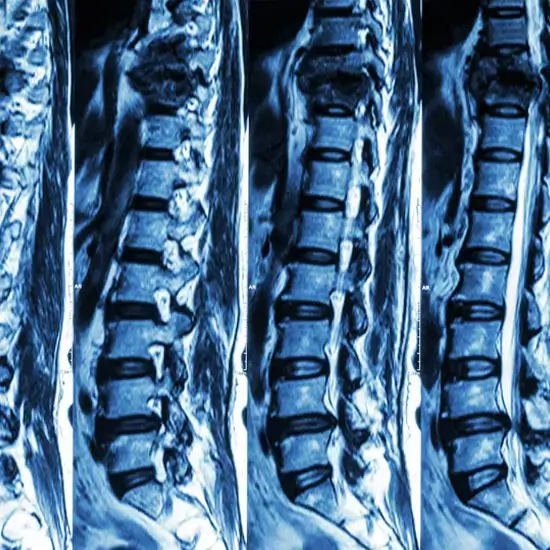

MR Angiography lumbar spine is an imaging procedure that uses contrast media to produce clear pictures of blood vessels of the lumbar spine region and its surrounding tissues. The lumbar region consists of 5 vertebrae i.e. L1 to L5.  This scan helps monitor the exact condition of blood vessels and other abnormalities in that area.

Doctors prescribe this scan to diagnose problems such as severe lower back pain and birth defects, evaluate the level of injury of the lower spine, and frequent lower back pain.